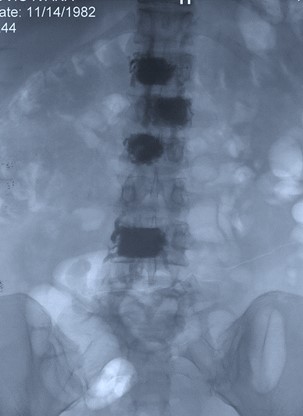

Multisegmentna Vertbroplastika

View the embedded image gallery online at:

https://www.klinikaelit.com/minimalno-invazivne-porcedure#sigProId42e6fa39e8